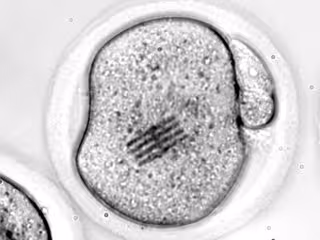

Embrión con un chip en su citoplasma

Embrión con un chip en su citoplasma - REMITIDA UGR

Con el chip dentro, los científicos han podido medir las fuerzas que reorganizan el interior del óvulo, es decir, su citoplasma, desde que se introduce el espermatozoide hasta que se divide en dos células.